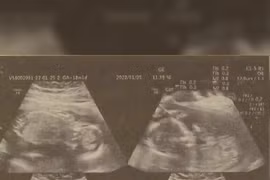

Dịch vụ độc đáo ứng dụng công nghệ in 3D của một bệnh viện ở Hồng Kông có thể giúp các bậc cha mẹ quá mong con hoặc bị khiếm thị có thể chạm vào em bé khi còn là bào thai.